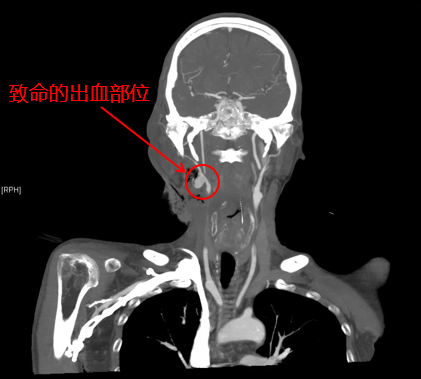

患者影像

耳鼻咽喉头颈外科主治医师陈雯婧、血管外科主治医师曹战江前来急诊会诊。患者的增强CT影像显示,出血部位近动脉血管,考虑肿瘤压迫动脉导致出血。病情急而重,陈雯婧请示科主任叶京英后,认为该患者下咽癌已属晚期,不具备根治性手术机会,动脉栓塞止血应为优先考虑方案。曹战江向科主任吴巍巍汇报了病情,决定立即为该患者进行动脉栓塞手术。